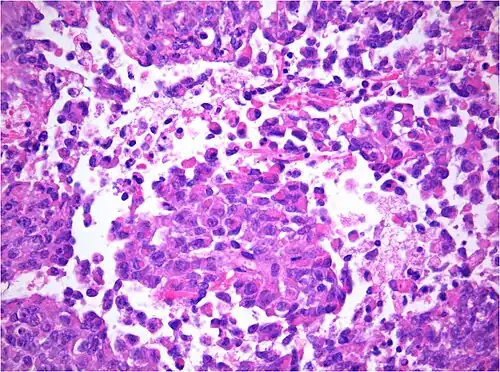

AT/RT and rhabdoid tumor share the term "rhabdoid" because under a microscope, both tumors resemble rhabdomyosarcoma.

AT/RT Histology with numerous rhabdoid tumor cells

The tumor histopathology is jumbled small and large cells. The tissue of this tumor contains many different types of cells including the rhabdoid cells, large spindled cells, epithelial and mesenchymal cells, and areas resembling primitive neuroectodermal tumor (PNET). As much as 70% of the tumor may be made up of PNET-like cells. Ultrastructure characteristic whorls of intermediate filaments are seen in the rhabdoid tumors (as with rhabdoid tumors in any area of the body). Ho and associates found sickle-shaped embracing cells, previously unreported, in all of 11 cases of AT/RT.[24]